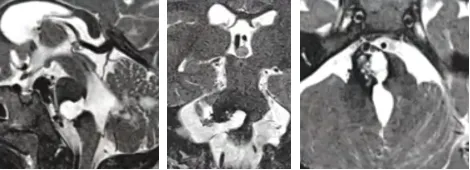

最终家属选择请德国巴特朗菲教授主刀。手术当日,娜娜看到许多不同年龄的患儿同样等待手术。当她苏醒时,听到母亲激动的声音:"娜娜的肿瘤终于切干净了!"

本案例选自巴特朗菲教授年会演讲案例集。需要特别说明的是,脑干出血患者确实面临较高风险,早期手术是最佳治疗选择。虽然患者对再次手术存在恐惧心理,但为挽救生命和支持她的家人,最终克服心理障碍接受手术。选择德国巴特朗菲教授主刀决策正确,术后影像学证实肿瘤全切,患者神经功能恢复顺利,不适症状逐步缓解,取得了令人满意的治疗效果。